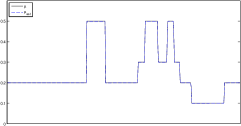

The data (see Figures 1 and 2) was generated in the diffusion model (1.2) using self-written (linear-basis) finite element code in MATLAB. For both examples, we took and used a uniform boundary condition . The simulated data were generated on a -grid and then down-sampled (by averaging) to to avoid inverse crime. After that, Gaussian noise with different intensities (standard deviations of and of the average signal value ) was added to the data.

Reconstruction results and error profiles at different noise levels can be seen in Figures 3 and 4. In both examples, the noise-free reconstructions are very accurate and contain mostly smoothing error. In the low-noise reconstructions, due to the fact that more regularization is necessary, some of the parameter variation is underestimated. In the high-noise examples, most detail in is lost since a lot of regularization is required to get reasonable results. The fine detail in can, however, still be recovered very accurately in both examples.